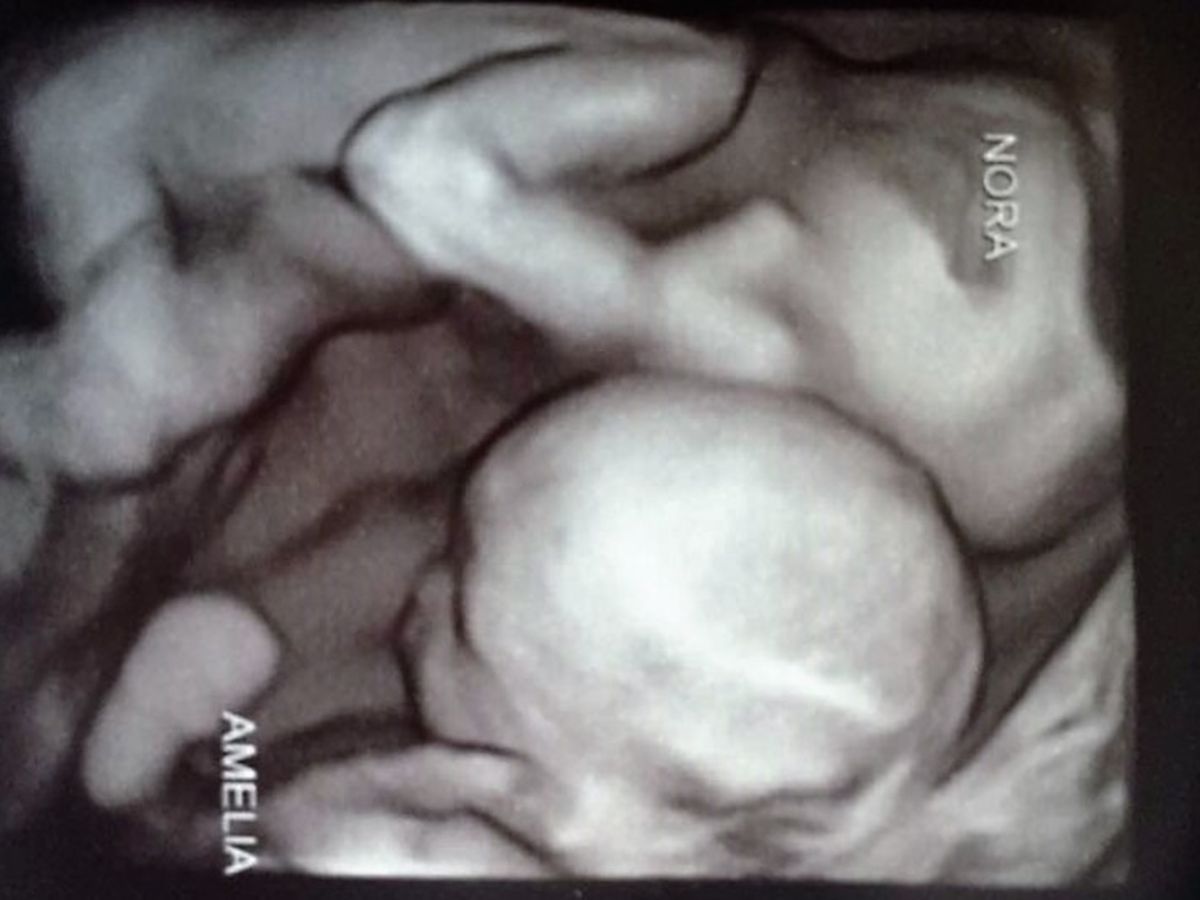

Marie and I (Justin) have some very sad news to share. Our beautiful identical twin daughters, Amelia Katherine and Nora Diana were diagnosed with twin-to-twin transfusion syndrome (TTTS) on Wednesday, August 17th 2016. There is only one real treatment available and so we went up to Minneapolis to have a Fetoscopic laser photocoagulation. We were told the surgery went well and we had the overwhelming faith we would indeed meet our beautiful daughters.

About a week after the surgery our little Amelia Katherine was taken to heaven at just 19 weeks old. She is truly so beautiful and such a strong fighter. She fought this terrible disease until the end. Her ultimate sacrifice was allowing her sister, Nora Diana, to have a fighting chance. Nora was not out of the woods and we are were told the next 3 weeks were a critical time for her. She was closely monitored and it looked like we were going to meet our Nora. On Tuesday, Sept 6th 2016, I came into the bedroom and was feeling my wife’s stomach as Nora was showing us her small little feet. She was always very active during the numerous ultrasounds. This made it almost impossible for the ultrasound techs to get the measurements they needed.

On Thursday, Sept 08, 2016 we went in for a routine ultrasound, but the news broke our hearts. Our sweet little Nora Diana had joined her angel sister, Amelia Katherine, in heaven. No words can describe how we feel.